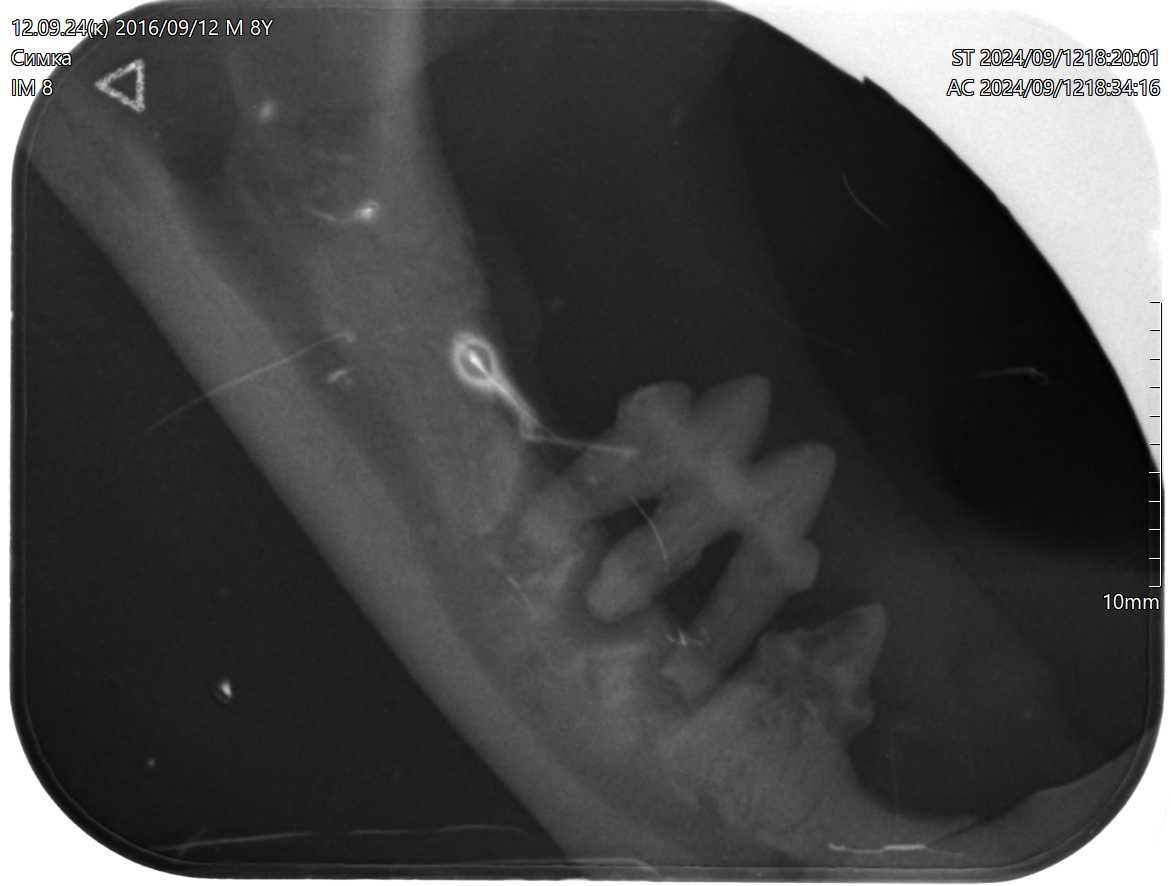

Геминация зубов у восьмилетней кошки бурманской породы